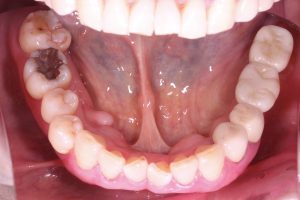

【71歳女性】

主訴:左下の顎がガクガクするとのことでご来院されました。

・左下奥歯がないところを咬めるようにしたい。

・保険適用の義歯を考えているが、インプラントも選択肢として考えている。

術前

今回は、左下奥にインプラントを2本を埋入しました。

上部構造は、メタルボンドクラウンという材料を使用しました。

(被せ物の内側が金属、外側の見える部分にはセラミックを使用)

外側が白いセラミックのため、見た目にも違和感がなく、噛む力に対しても強い材料となっております。

左下1番奥の親知らずに関しては、お口を開ける際の動きの阻害をしており、顎関節の負担になっていたため、患者さまに説明後、抜歯を行なっています。